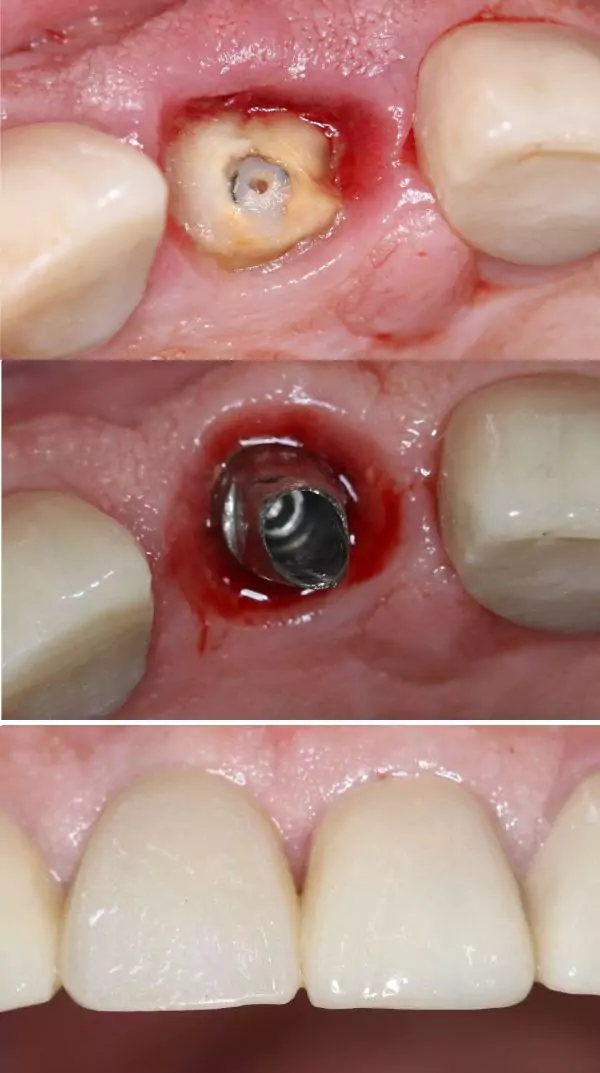

Before & After Transformations

Smile Gallery

Smile Journey Highlights